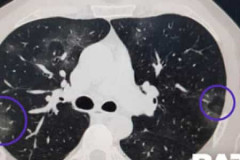

Ովքե՞ր կարող են այս օրերին այցելել Արցախ. ներկայացնում է ՀՀ փոխոստիկանապետը Կորոնավիրուսով վարակված զինծառայողներից միայն մեկն ունի թույլ արտահայտված ջերմու... Հակառակորդը շփման գծում հրադադարի պահպանման ռեժիմը խախտել է 150 անգամ Կորոնավիրուսից մահացած 72-ամյա կնոջը փակ դագաղով են հուղարկավորելու Ասում են` կորոնավիրուսի համար հայատառ գրողները պակաս խոցելի խումբ են․ նախարար Ցիկլոն է մոտենում, սպասվում է անձրև․ Գագիկ Սուրենյան Գետափ-Մարտունի ճանապարհին «Պեժոն» բախվել է երկաթյա արգելապատնեշին. 20-ամյա ուղեւ... Կորոնավիրուսի վարակման 43 նոր դեպք է գրանցվել. հաստատված դեպքերի թիվը հասավ 372-ի Արմավիր քաղաքի 50-ամյա բնակիչը դանակահարել է 35-ամյա տղամարդուն (տեսանյութ) ՀՀ տարածքում ճանապարհները հիմնականում անցանելի են. Լարսի ճանապարհը բաց է միայն բ... Որքանո՞վ օգտակար կլինի Արթուր Վանեցյանի հաջորդ քայլը Արցախ մտնող անցակետերում կանգնեցնում են բոլոր մեքենաները, ստուգում են փաստաթղթեր... Facebook-ում մտադիր են կորոնավիրուսի մասին տեղեկացնել ամբողջ աշխարհի օգտատերերին Ֆելիքս Ցոլակյանը իր մեկ ամսվա աշխատավարձը փոխանցել է կորոնավիրուսի դեմ պայքարի հ... Ինչ եղանակ է սպասվում առաջիկա օրերին Վարակվածների մեջ դպրոցահասակ երեխաներ կան. Արսեն Թորոսյան Կորոնավիրուսի ամենամեծ թվով դեպքեր են գրանցվել Երեւանում, Արմավիրում, Արարատում ... COVID-19 հետազոտման թեստի արդյունքում երեք զինծառայողների մոտ ախտորոշվել է կորոն... Վանում 4․7 մագնիտուդ ուժգնությամբ երկրաշարժ է գրանցվել Դիլիջանի ոլորաններում ավտոմեքենան 100 մետր գլորվել է ձորը. վարորդը և ուղևորը մահ... Երկու պացիենտի վիճակը ծայրահեղ ծանր է. Նիկոլ Փաշինյան Կորոնավիրուսի վարակման 25 նոր դեպք է գրանցվել. հաստատված դեպքերի թիվը հասավ 290-... Ինչպես է կորոնավիրուսն աստիճանաբար տարածվում հիվանդի թոքերում. Baza (տեսանյութ) Լարսի ճանապարհը բաց է միայն բեռնատարների համար Թոքաբորբով 36 հիվանդներից երկուսի վիճակը ծայրահեղ ծանր է. Արսեն Թորոսյան Վանեցյանի քայլը կկասեցնի անկանոն շրջապտույտը ԲՀԿ խմբակցությունը հատուկ նիստում քննարկել է կորոնավիրուսի հետևանքով ստեղծված իր... Դոլարի փոխարժեքի վերելքը չի դադարում. Եվրոն նույնպես թանկացել է Հակառակորդի նախահարձակ գործողությունից տուժած զինծառայողներին հատուցում կտրվի Հրշեջ-փրկարարները մարել են 14.4 հա խոտածածկ տարածքներում բռնկված հրդեհները